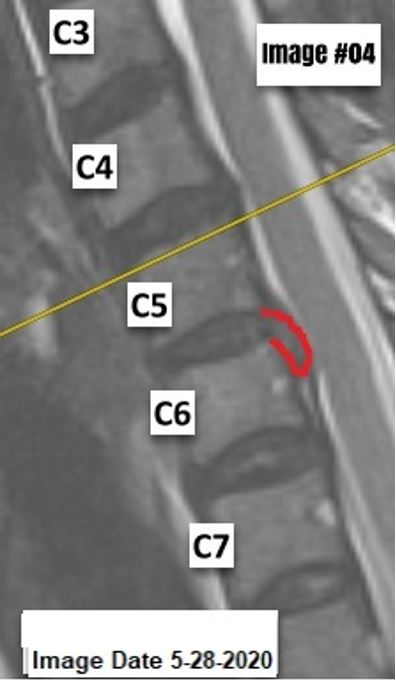

MRIs Colorized for You

This level of demonstrability has been the single biggest "game-changer" since I have been consulting for over 2 decades. Credentials make other DCs irrelevant, this makes MD specialists irrelevant if the lawyer is trained accordingly. This is not about interpreting your images, that is up to you. This service is about making your interpretation demonstrative, or easy to identify for the lay-person.